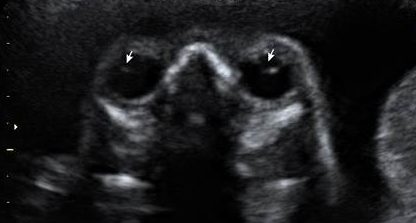

Microftalmia é a alteração de desenvolvimento caracterizada pela redução do tamanho do bulbo ocular. O vídeo acima está publicado no…